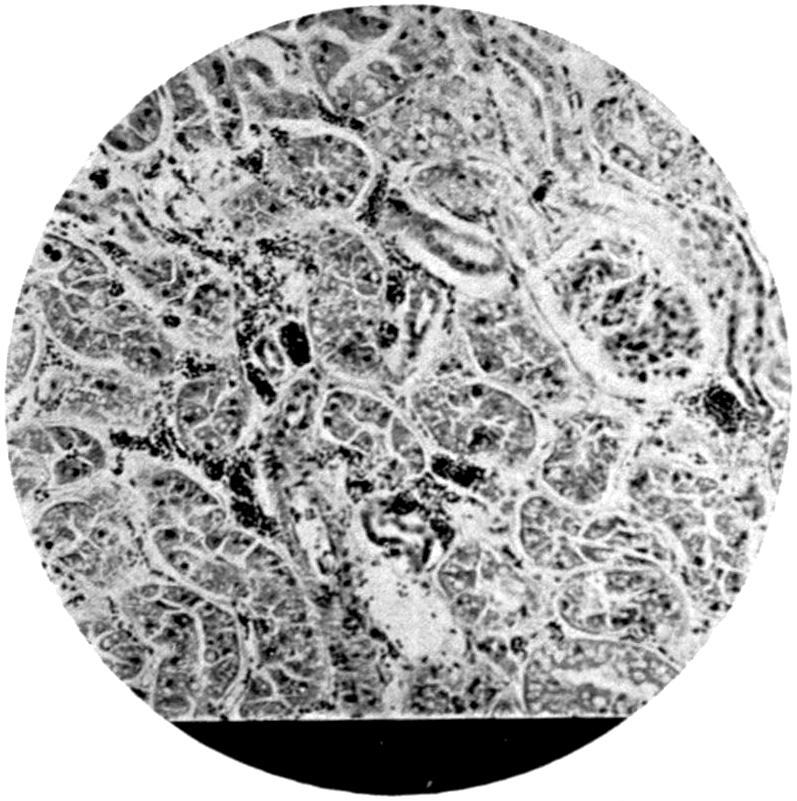

Plate IV. 276